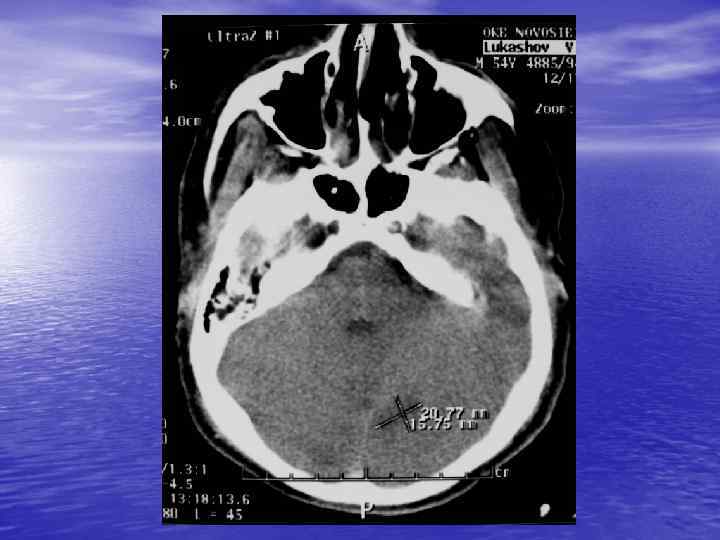

С появлением компьютерного томографа стало возможным визуализировать тканевые структуры головного мозга

Преимущества спиральной КТ: ü Возможность проведения исследования с болюсным ü ü ü ü ü контрастированием Высокая разрешающая способность; Высокая скорость исследования; Получение высококачественных изображений костных структур; Возможность обследования всего тела; Возможность проведения исследования больных под наркозом; Возможность детальной оценки состояния крупных и периферических сосудов в условиях искусственного контрастирования; Высокая информативность метода при черепномозговых травмах в остром периоде; Ранняя диагностика ишемических и геморрагических инсультов; Метод выбора для диагностики заболеваний легких; Планирование лучевой терапии.

недостатками КТ являются: ü Высокая лучевая нагрузка на пациента. ü Необходимость применения ü ü водорастворимых йодсодержащих контрастных препаратов. Отсутствие визуализации спинного мозга. Затруднение визуализации задней черепной ямки, краниовертебрального перехода.